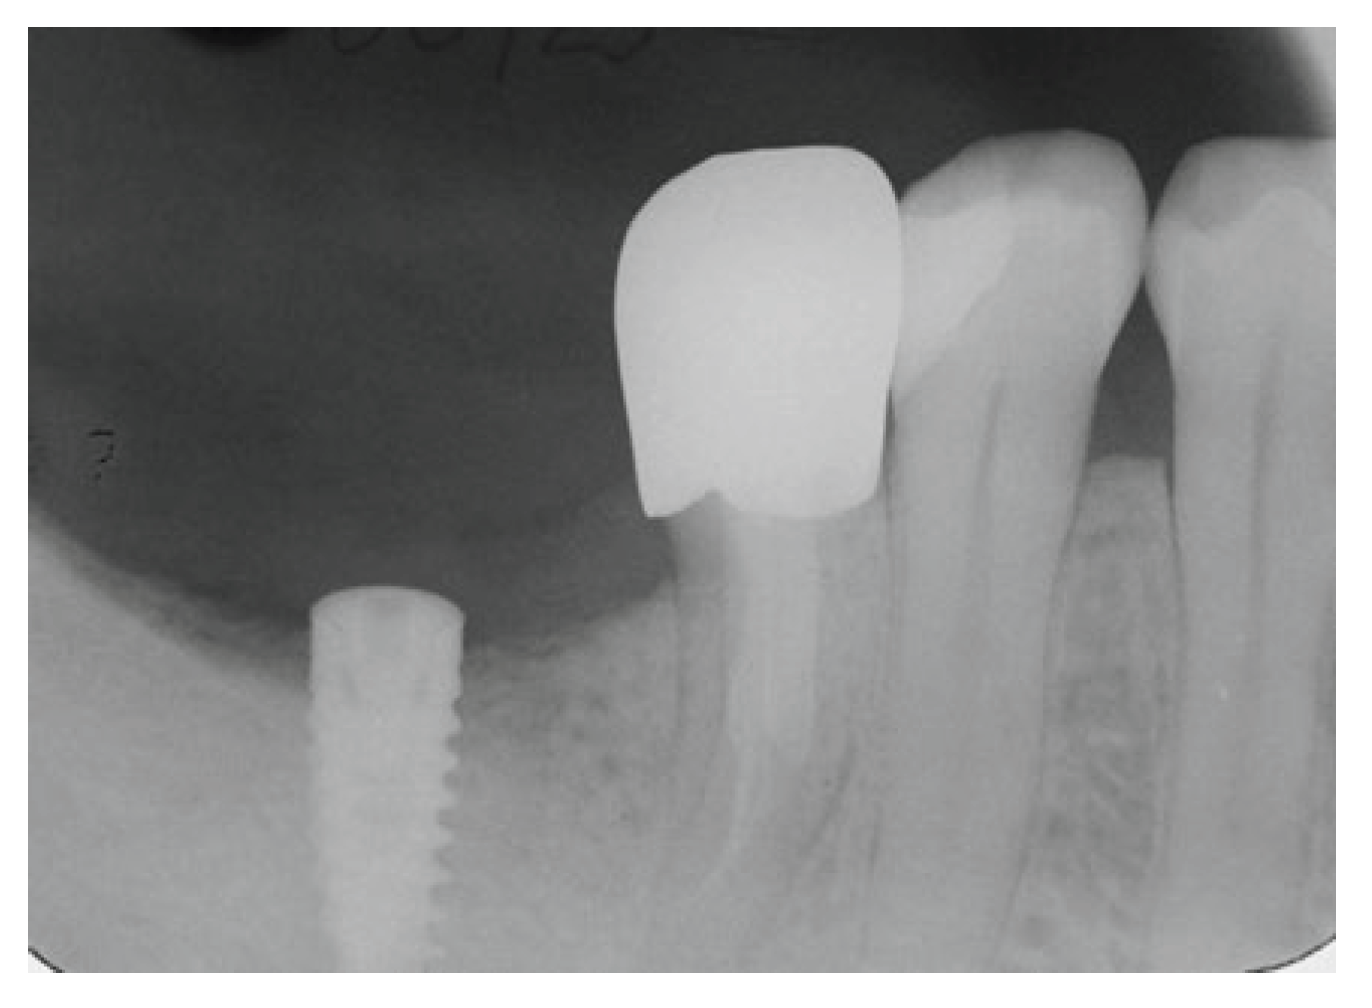

On the other site, namely in the area of #46-#47, according to CBCT measurements, it was decided to place only one MIS SEVEN implant having a 10 mm length and 4.20 mm diameter for replacement of missing teeth #47 and distal root of #46. Implant placement was done routinely, radiograph taken 4 months after placement showed an excellent healing and the patient referred to GP for the final placement of implant supported restoration (Figure 8)

Figure 5. CBCT of the lower right region of the mandible for studying bone dimensions and anatomical elements for implant placement.